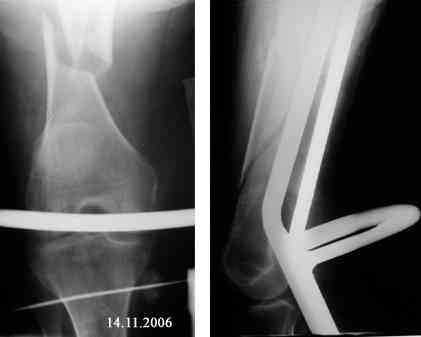

Представляю вашему вниманию снимки в динамике

Закрытый АВФ в этой ситуации может решить Ваши проблемы. Главное не размещать в проксимальном отделе бедра спицевую опору. Чаще всего именно там возникают воспалительные осложнения. Выход: либо "опустить" проксимальную опору к перелому, либо сделать ее стержневой. Срок фиксации правда 3 - 4 мес. На операции после восстановления оси отломок желательно "пришить" сквозной спицей с упором или консольной спицей.

В подобном случае чрескостный аппарат следующей компоновки является вариантом выбора:

1 2 4 6 5 7 3

I,8,90; II,11,90 -- IV,9,90 -- VI,3-9; VII,9-3; VIII,8,90 -- VIII,3-9

1/3 210 2/3 210 180 2/3 180

Размеры опор, конечно, указаны условно.

Вместо IV,9,90 может использоваться IV,8,90 или IV,10,90 - в зависимости от остаточного смещения

проксимального фрагмента.

Спицу VI,3-9 используется для репозиции и фиксации крупного костного осколка.

Дистальную опору VIII,3-9 через 6-8 нед. можете демонтировать. Если вместо стержня-шурупа II,11,90

используете II,11,120 с фиксацией ко второй опоре, то в эти же сроки можете удалить проксимальную

опору, "переключив" I,8,90 ко второй опоре.